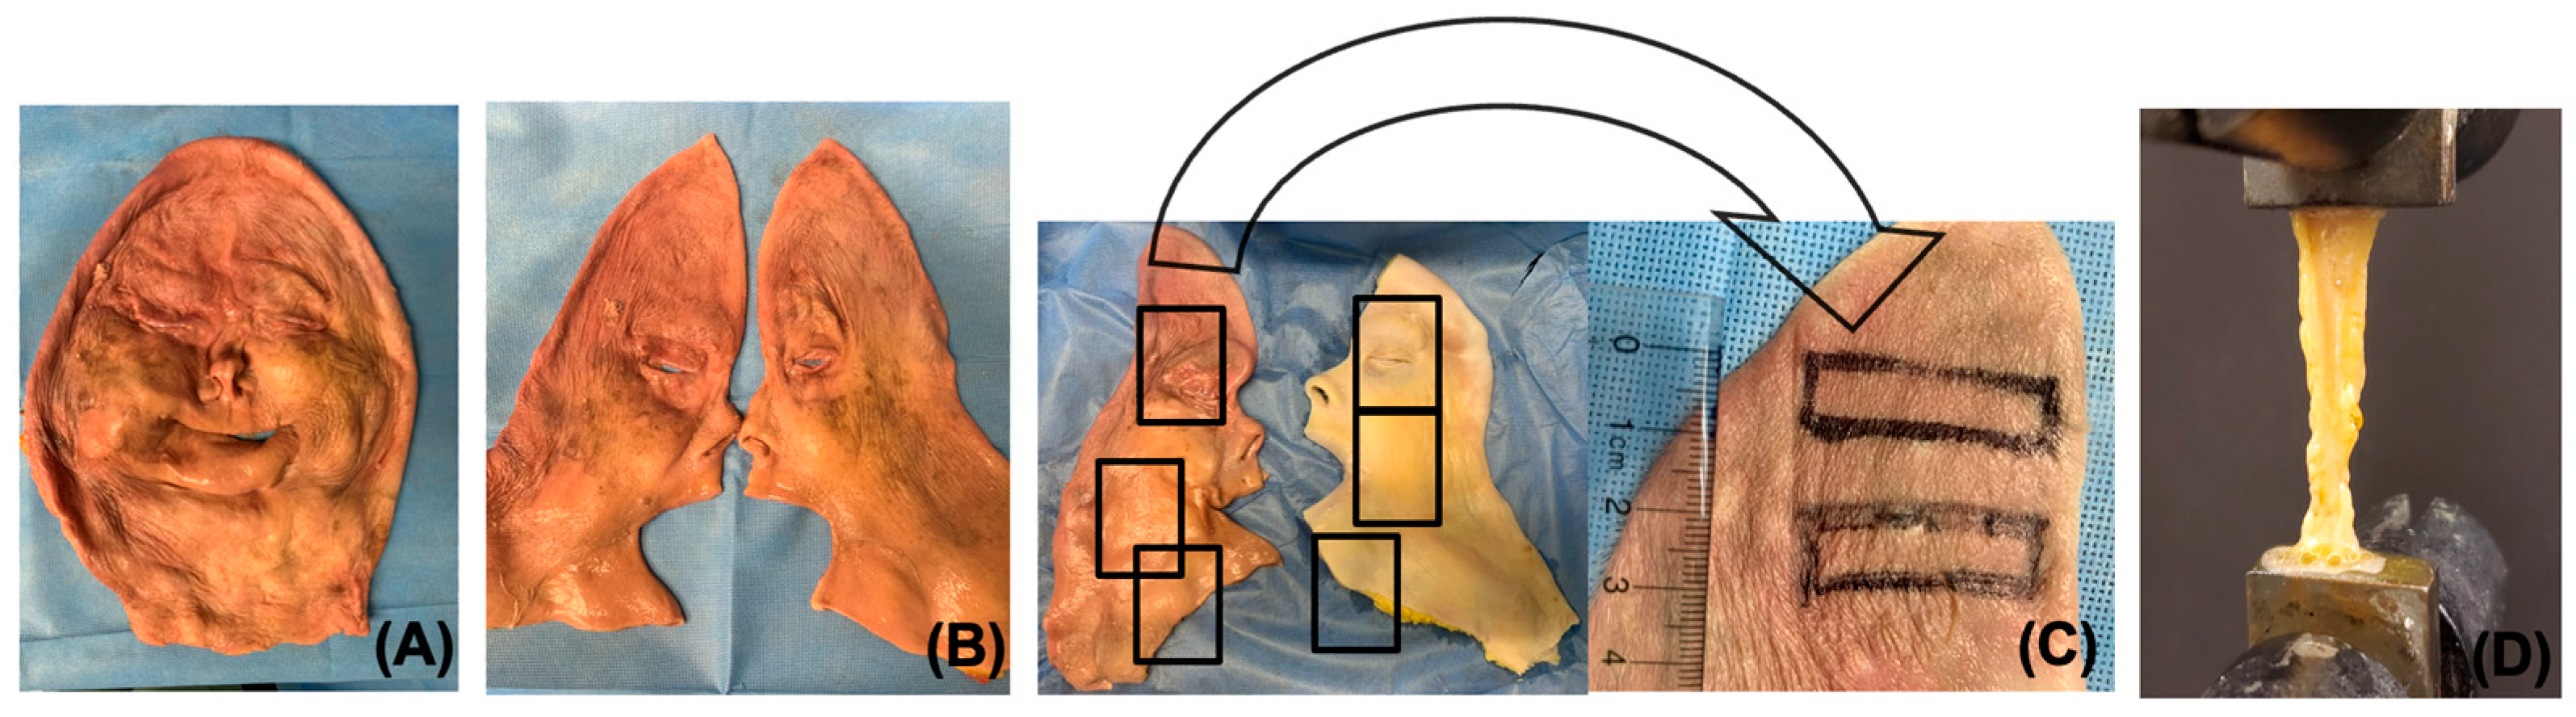

2.1. Tissue Procurement

2.2. Decellularization of Facial Grafts

2.8. Mechanical Testing of Decellularized Grafts